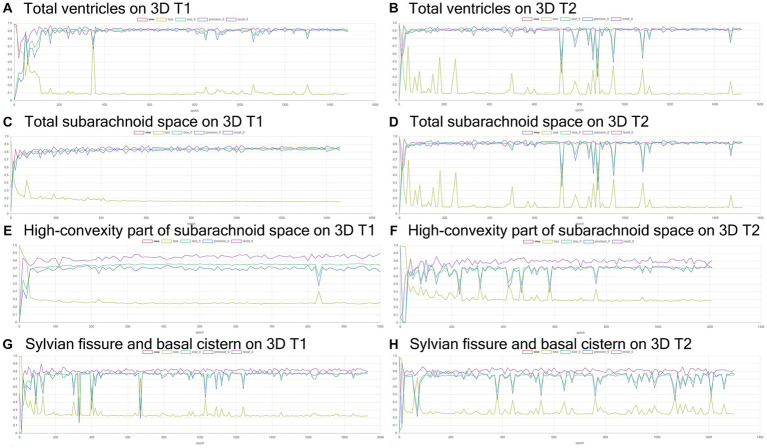

Volumetric semantic segmentation

Training and internal validation of the 3D U-Net model for semantic segmentation were repeated over 1,000 times (Figures 4–7; Supplementary Figures S1, S2). Overall, the intracranial CSF space, total ventricles, total SAS, Sylvian fissure and basal cistern, and the high-convexity SAS were segmented fully automatically from 3D T1-weighted (Figure 8) and T2-weighted MRIs (Figure 9). There was no significant difference between manually and automatically segmented volumes of the total ventricles, total SAS, high-convexity SAS, and Sylvian fissure and basal cistern (Table 3). Among the segmented regions, the mean Dice scores for the total ventricles were highest (0.85 from T1 and 0.83 from T2), those for the Sylvian fissure and basal cistern were second highest (0.70 and 0.69), and those for the high-convexity SAS were lowest (0.68 and 0.60). The mean Dice coefficient scores for all of the regions segmented from the T1-weighted image were superior to those from the T2-weighted image. The mean differences between the manually and automatically segmented volumes of the high-convexity SAS were smaller (T1 and T2; 3.6 mL and 4.2 mL) than those of the Sylvian fissure and basal cistern (5.3 mL and 8.3 mL).